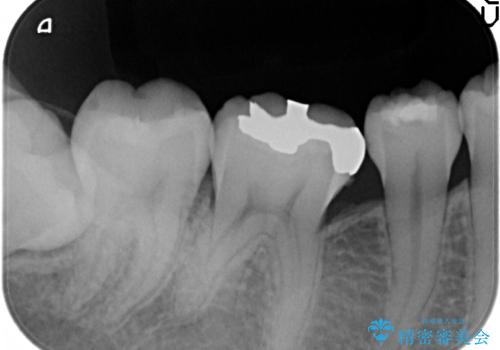

- 銀歯を白くして欲しいといらっしゃった方の症例です。

銀歯及び虫歯を除去後、セラミックインレーによる修復を行いました。